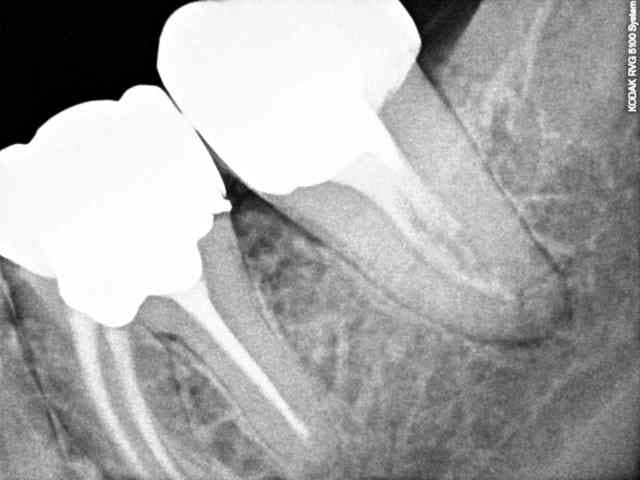

Un patient se présente avec une lésion carieuse importante sur 47. Je fait une rétroalvéolaire. La forme de l'endodonte m'interpelle, je curete et ne fait pas d'effraction pulpaire, donc je met un CVI. Le patient fait une pulpite, je fait le traitement, j'ai trouvé un très gros canal distal que je pensais unique, puis un tout petit mésial bien centré dans le sens linguo vestibulaire.

Ai-je tout obturé?

PS: J'ai mis la radio de la dent controlatérale un confrère n'avait visiblement pas mieux compris l'anatomie canalaire.